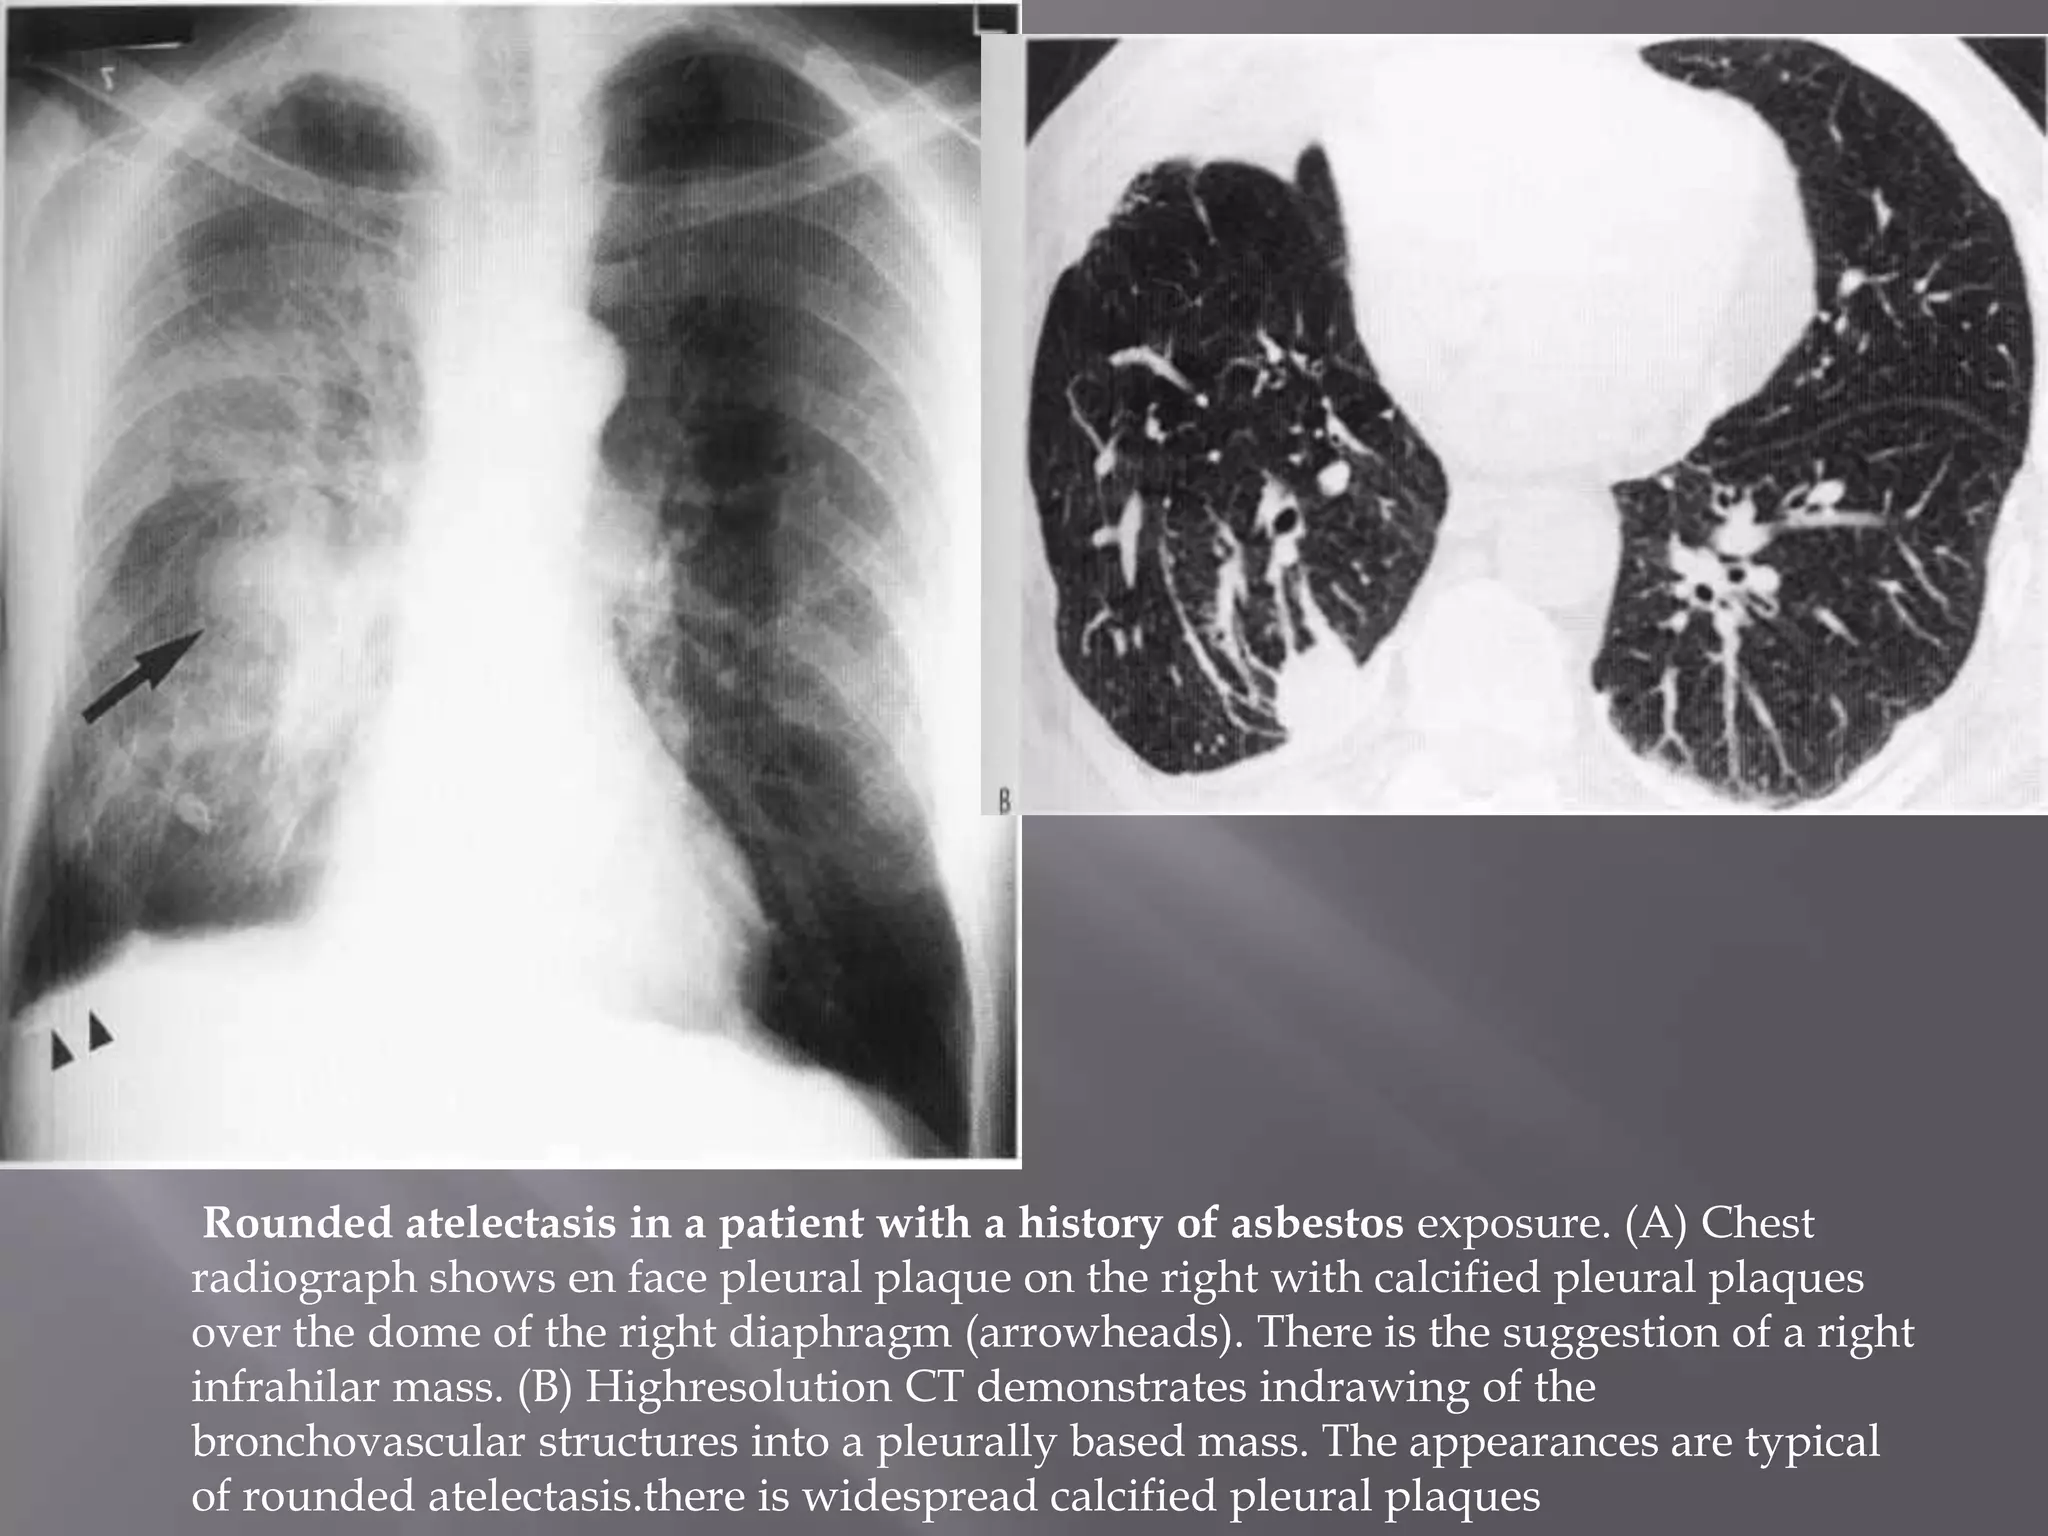

 This is an unusual form of pulmonary collapse which may

be misdiagnosed as a pulmonary mass.

 Appears on plain film as a homogeneous mass, upto 5 cm in

diameter, with ill-defined edges

 Always pleural based & associated with pleural thickening

 Vascular shadows may be seen to radiate from part of the

opacity, resembling a comet's tail.

 The appearance is caused by peripheral lung tissue folding

in on itself

 Often related to asbestos exposure, but may occur secondary

to any exudative pleural effusion

 It is not of any pathological significance.

 CT appearance is usually diagnostic, & enables

differentiation from other pulmonary masses

Rounded atelectasis in a patient with a history of asbestos exposure. (A) Chest

radiograph shows en face pleural plaque on the right with calcified pleural plaques

over the dome of the right diaphragm (arrowheads). There is the suggestion of a right

infrahilar mass. (B) Highresolution CT demonstrates indrawing of the

bronchovascular structures into a pleurally based mass. The appearances are typical

of rounded atelectasis.there is widespread calcified pleural plaques

 This isan unusual form of pulmonary collapse which may be misdiagnosed as a pulmonary mass.  Appears on plain film as a homogeneous mass, upto 5 cm in diameter, with ill-defined edges  Always pleural based & associated with pleural thickening  Vascular shadows may be seen to radiate from part of the opacity, resembling a comet's tail.  The appearance is caused by peripheral lung tissue folding in on itself  Often related to asbestos exposure, but may occur secondary to any exudative pleural effusion  It is not of any pathological significance.  CT appearance is usually diagnostic, & enables differentiation from other pulmonary masses

Rounded atelectasis ina patient with a history of asbestos exposure. (A) Chest radiograph shows en face pleural plaque on the right with calcified pleural plaques over the dome of the right diaphragm (arrowheads). There is the suggestion of a right infrahilar mass. (B) Highresolution CT demonstrates indrawing of the bronchovascular structures into a pleurally based mass. The appearances are typical of rounded atelectasis.there is widespread calcified pleural plaques